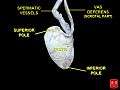

Transverse section through the left side of the scrotum and the left testis. Testis, spermatic vessels and vas deferens

Testis, spermatic vessels and vas deferens- Testicular artery and vein